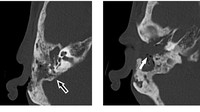

Pemeriksaan klinis menunjukkan lesi erosif atau kerusakan di belakang telinga kanan dengan bekas luka operasi sebelumnya. Setelah mengamati lebih dekat, dokter mengamati beberapa benda asing putih yang mudah bergerak di telinganya dan diambil untuk diperiksa lebih lanjut. Pemeriksaan otoskopi menunjukkan pembengkakan liang telinga luar dan keberadaan larva lalat (miasis) atau belatung. Kasus ini diterbitkan di jurnal Cureus dengan judul 'Aural Myiasis: A Case Report on a Rare Entity' pada 2020. (Foto: Journal Cureus)

Untuk mencegah komplikasi, pasien langsung menjalani operasi dengan pengangkatan (reseksi) larva, sekuester tulang nekrotik, dan mukosa yang terkena. Pascaoperasi, pasien mendapat amoksisilin–klavulanat untuk mencegah infeksi sekunder serta terapi lokal berupa suspensi oksitetrasiklin dan hidrokortison. Pada kontrol empat bulan pascaoperasi, tidak ditemukan kekambuhan. (Foto: Journal Cureus).